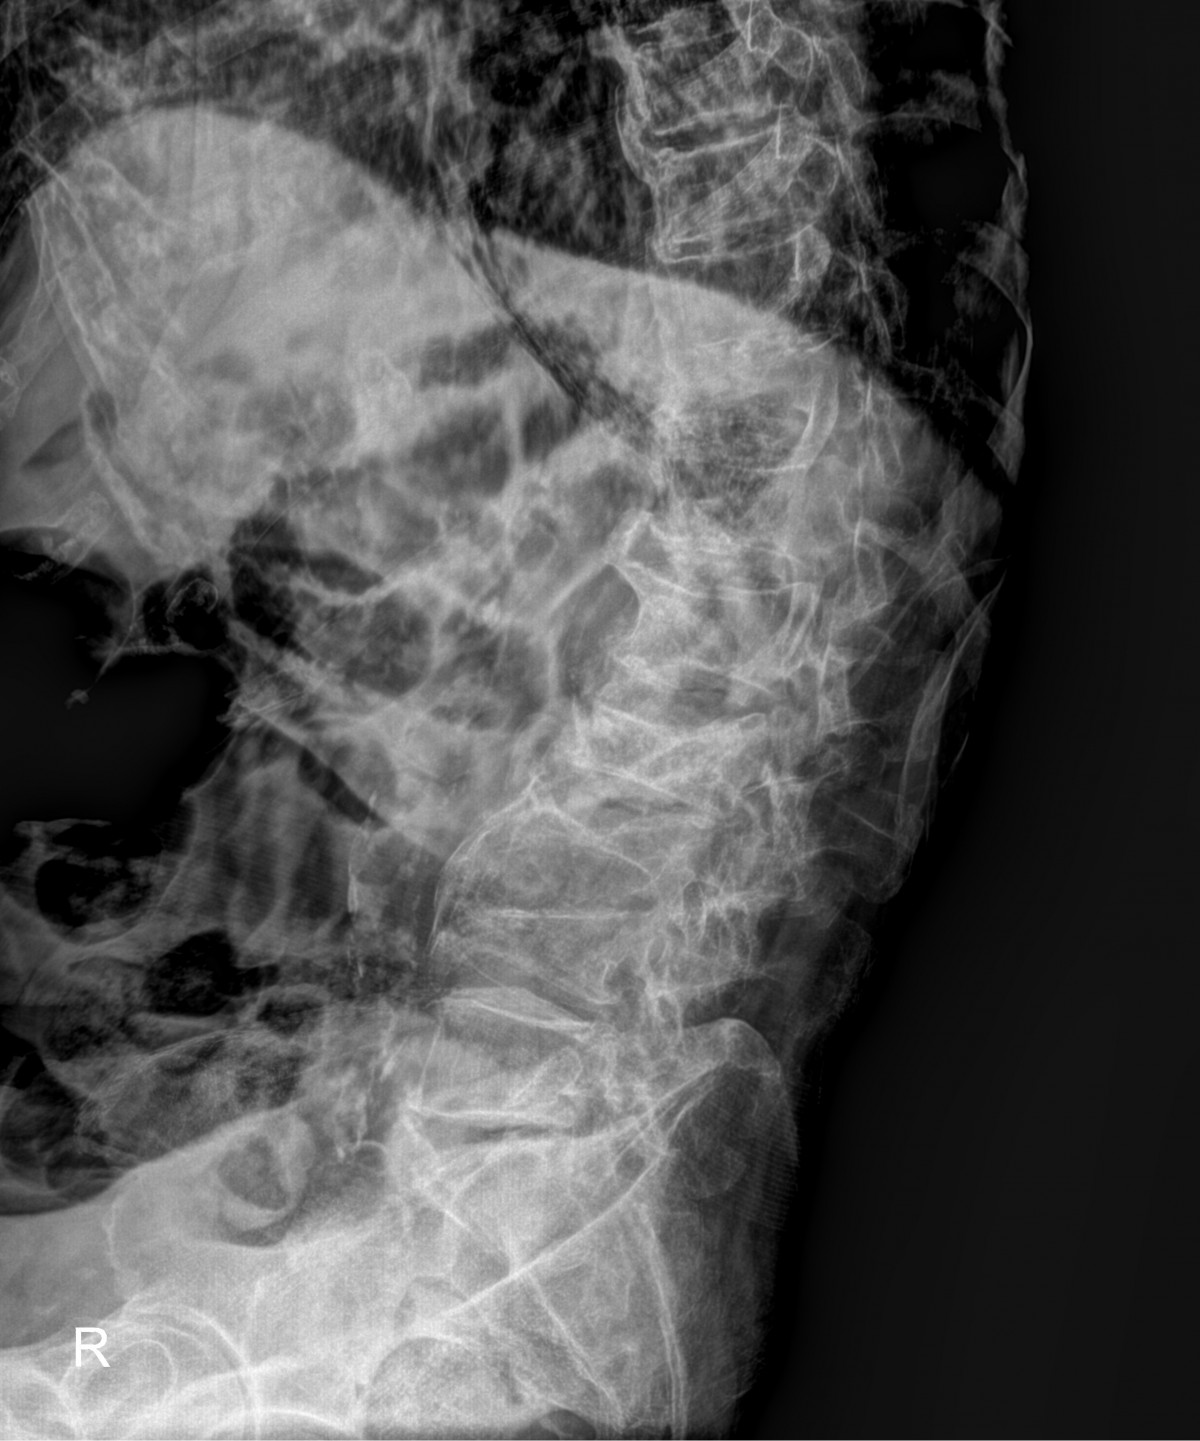

정지영원장님 허리 골절 골시멘트 성형술 김창O 환자

dae765e4d9ac96aee867c9d6292d8784_1758007978_2855.jpg